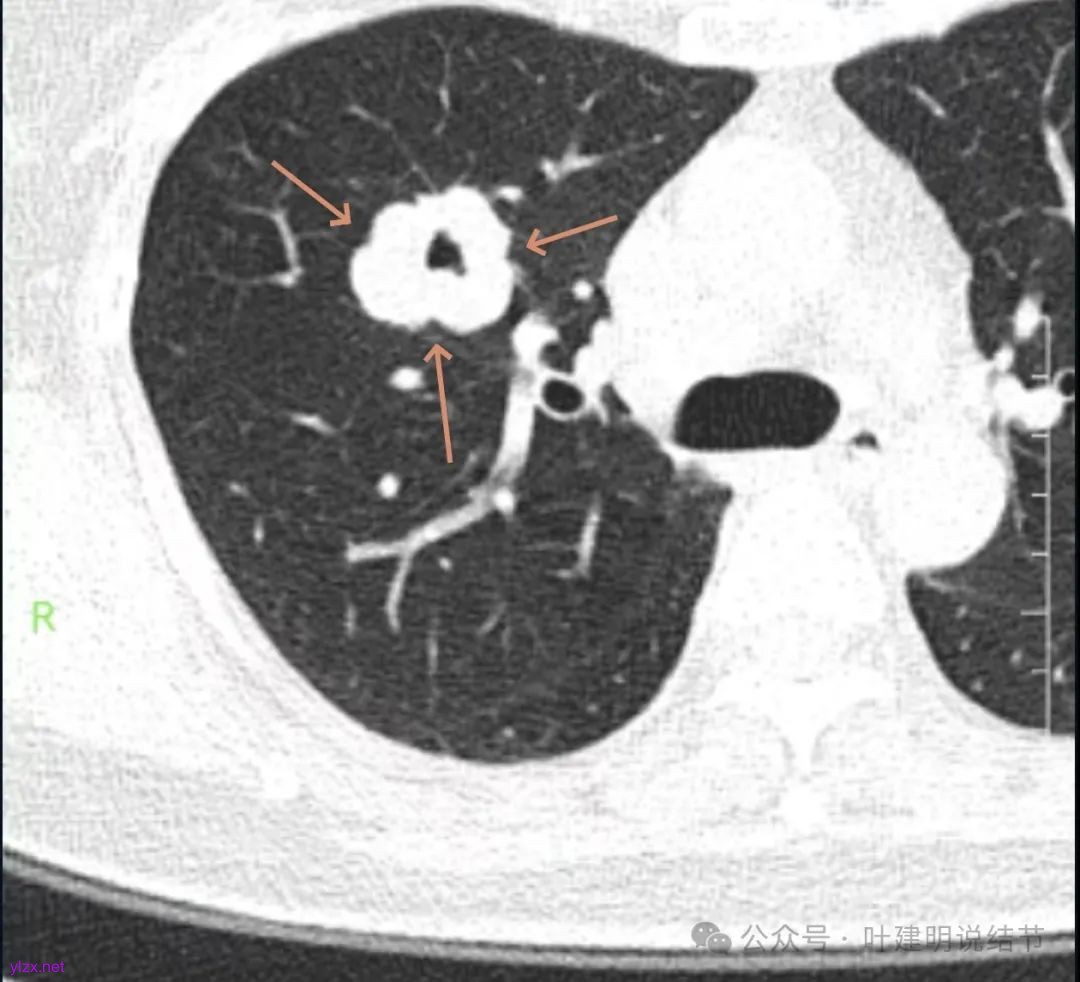

咳嗽近三周,CT检查提示右肺上叶空洞病变。

影像展示与分析:

你的右上叶这个病灶基本上肯定是肺癌,要尽快处理。从影像上看有以下特点:1、整体轮廓清楚,不似普通炎症的周围有晕或阻塞性改变;2、边缘明显的浅分叶,总体上的感觉膨胀性明显,不管哪个层面看上去都是鼓鼓的;3、边缘区域有磨玻璃成分而且也是分叶状的;4、部分层面见血管进入;5、空腔病灶的壁厚薄不均,内壁不光滑。我考虑中低分化肺癌,由于腔静脉旁有明显肿大淋巴结,需要进一步完善增强CT以及PET-CT检查以明确有无远处转移,是否仍可手术治疗(从病灶本身来说是可以肺叶切除治疗的)。要尽快处理。意见供参考!